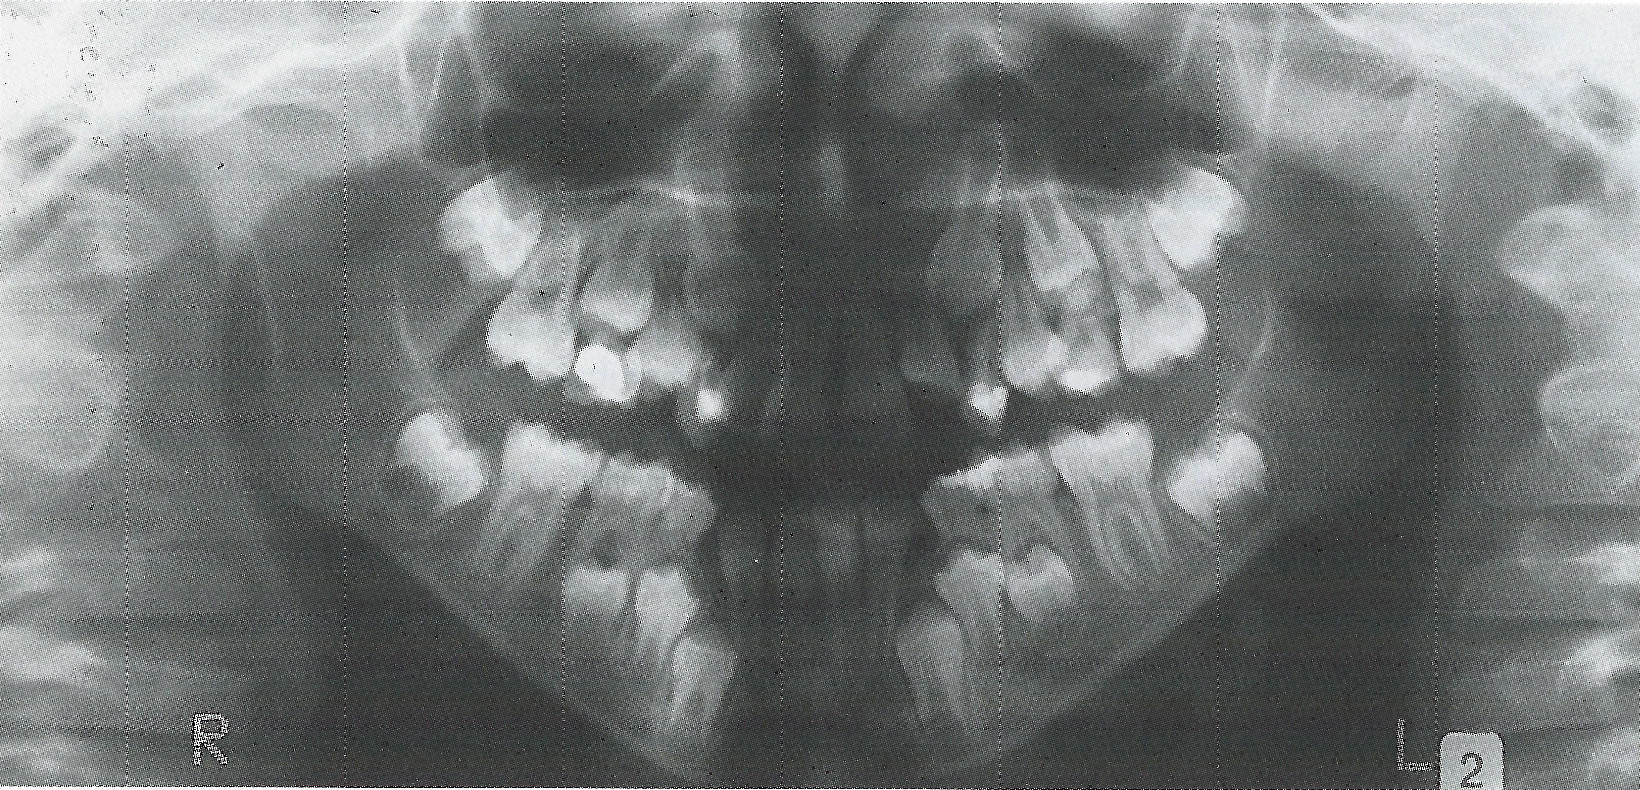

Bei Abnahme der Apparatur war der rechte obere Milcheckzahn gering, der linke mäßig gelockert. Zu diesem Zeitpunkt wurde ein Orthopantomogramm angefertigt, das deutliche Wurzelresorptionen der betroffenen Zähne erkennen läßt (Abb. 15).

• Ankylose Abb.15

Abb. 15 Orthopantomogramm mit deutlichen Resorptionen an den Wurzeln der Milcheckzähne.